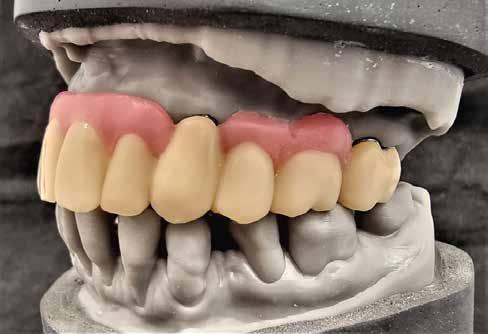

1–2. képek: Kiindulási helyzet.

3. kép: Új teleszkópos fogpótlás az 16, 15, 13, 23 és 27 fogakra.

Teleszkópos munka, élő eset bemutatásával ismertetem, mi az, ami már lehetséges. A munkaasztal-szkenneren kívül bevetésre került a digitális munkafolyamatok során egy intraorális szkenner (IOS) is. A 3D nyomtatású testek gyártása a laboratóriumban LCD- és DLP nyomtatókkal történt. A fémes komponenseket szelektív lézerolvasztásos (SLM) technológiával készíttettük.

Kiindulási helyzet

A páciens látlelete a következő:

• krónikus általános parodontitis

• a 24-től terjedő parodontális fekély

• hatástalan kapcsos felső fogpótlás (1-2. képek)

Terápia

A kezelőorvos (dr. Werner Knapp, Würzburg) ennek alapján a következő terápiát javasolta:

• a 24-es fog extrakciója, illetve az 12 és 22 fogak extrakciója előrehaladott szövetveszteség okán

• szisztematikus parodontitis-terápia

• új, teleszkóp-elhorgonyzású felső fogpótlás az 16, 15, 13, 23 és 27 fogak felhasználásával (3. kép)